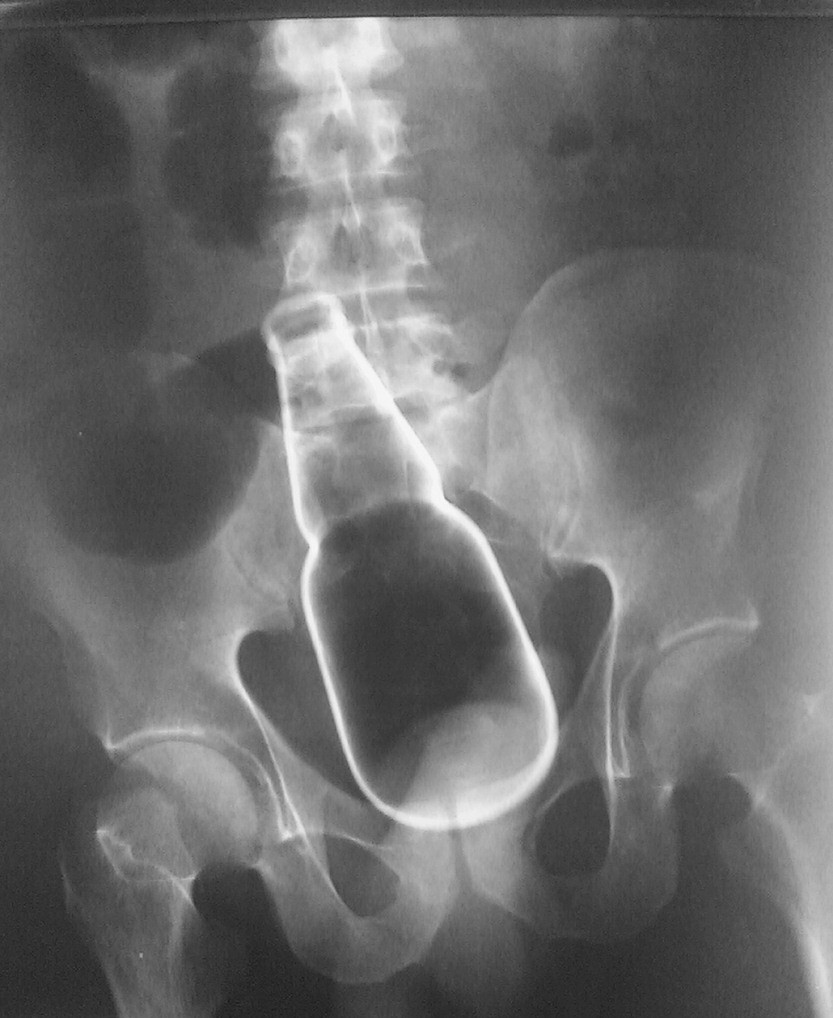

의외로 엉덩이에 넣으면 안되는 것들